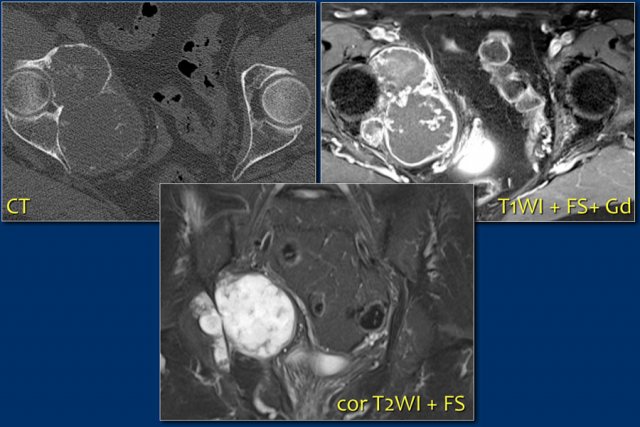

On the left a patient with a chondrosarcoma of the right acetabulum.

On the CT expansion and subtle calcifications are present.

On the coronal T2-weighted image the tumor is seen as a large lobulated mass with very high SI, which is typical for chondroid tumors.

The T1-weighted image after Gd shows typical peripheral nodular enhancement.

In the center there is no enhancement.

This is probably due to a large myxoid component. .